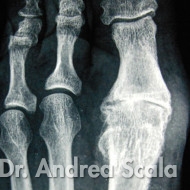

IMG 3 – La radiografia mostra che il fallimento dell’intervento dell’alluce valgo si accompagna all’alluce rigido.